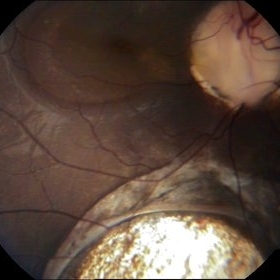

Choroidal Coloboma

10-year-old female patient presented with loss of vision.

Photographer: Drashti Netralaya,Dahod

Imaging device: Zeiss ff450

Condition/keywords: choroidal coloboma